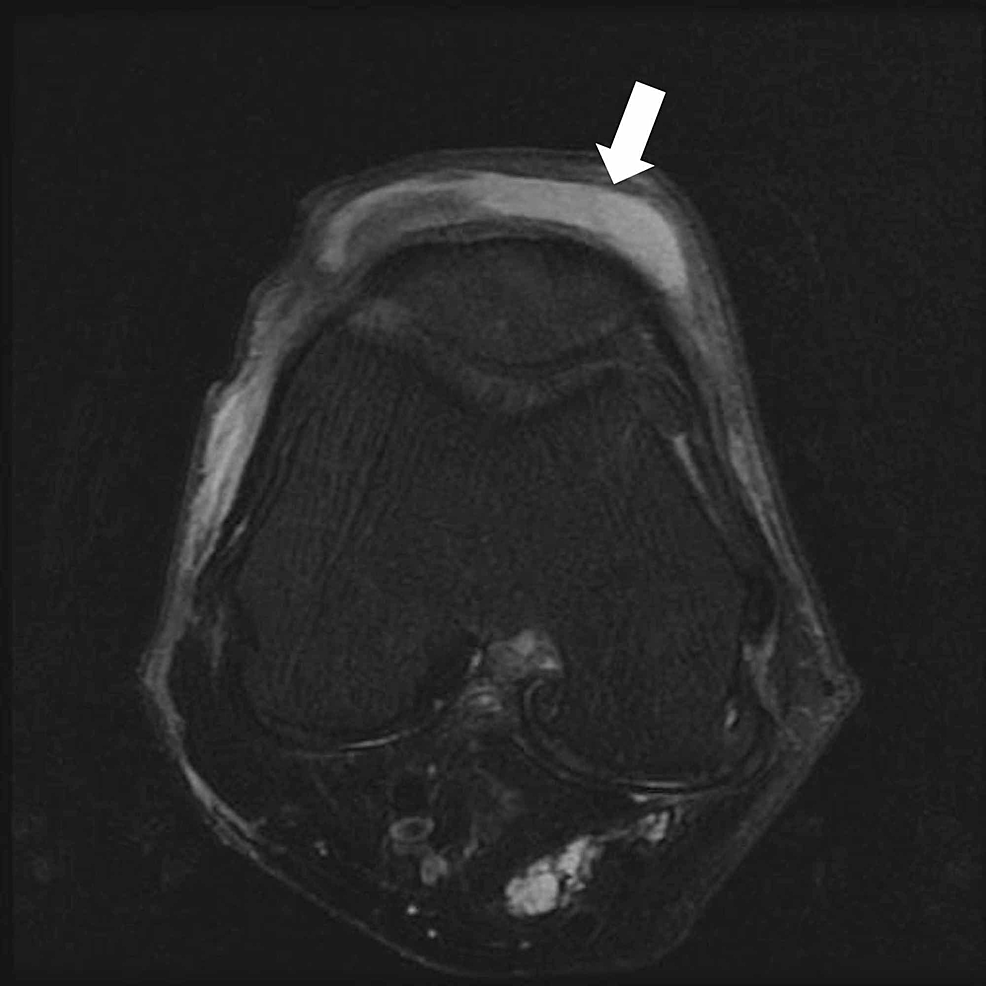

Prepatellar bursitis Primal Physiotherapy